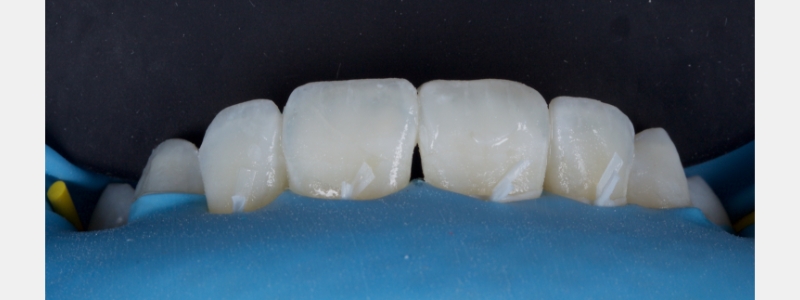

A diagnosis of altered passive eruption (APE) alongside tooth surface loss (TSL) secondary to parafunction was made for a referred female patient in her early 20s who complained of having“short, fat, baby teeth.” Due to her age, she was treated with a simple gingivectomy (after bone sounding), nightguard vital bleaching (NGVB), and additive edge bonding.

The worn incisal edges were restored with edge bonding, a new technique for restoring worn dentition. This should be regarded as a multiple Class IV restoration.